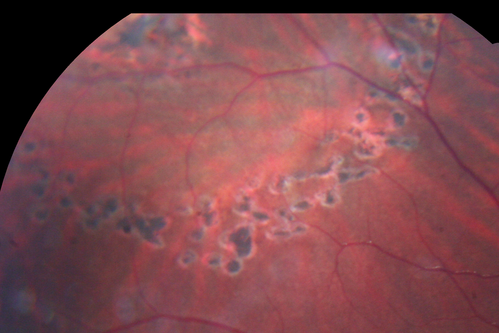

Asymptomatic Laser Demarcated Retinal Detachment has Spontaneously Re-attached 6 Months After Laser

Spontaneously Re-attached Detached Retina